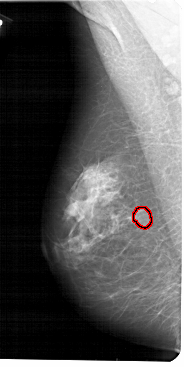

A_1512_1.LEFT_MLO

LEFT_MLO LINES 5491 PIXELS_PER_LINE 2746 BITS_PER_PIXEL 12 RESOLUTION 43.5 OVERLAY

FILE: A_1512_1.LEFT_MLO.OVERLAY

TOTAL_ABNORMALITIES 1

ABNORMALITY 1

LESION_TYPE MASS SHAPE OVAL MARGINS CIRCUMSCRIBED

ASSESSMENT 3

SUBTLETY 4

PATHOLOGY BENIGN

TOTAL_OUTLINES 1